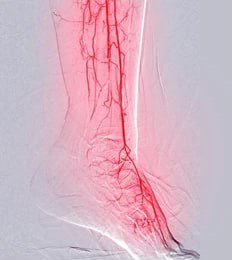

- Doppler Ultraschall: Bildgebungsstudie unter Verwendung von Klangwellen, die Bilder von Arterien erzeugen, die vorhandene Blockaden aufgrund des Plaque-Aufbaus hervorheben.

- Angiographie: Die Farbstoffinjektion über den Katheter in den Blutkreislauf beleuchtet unter Röntgenführungsverfolgungsströmungsweg, die verengte/blockierte Regionen identifizieren.